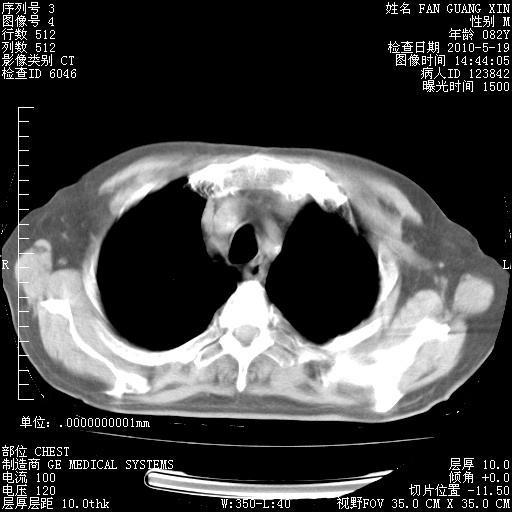

治疗3周后的肺部CT

治疗3周后的肺部CT纵隔窗